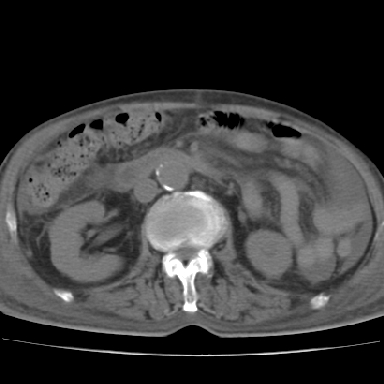

以下是引用qian在2006-12-4 19:11:00的发言:[br]胸腔和腹腔内均见有液性影,肝上极包膜下有一较大椭圆形低密度影,密度均匀,边缘清晰,结合病史考虑术后肝脓肿并胸腹腔积液。

以下是引用chry3在2006-12-4 21:05:00的发言:[br]应该往上扫几层,我考虑膈下脓肿。[br]大家考虑:胃部手术怎会造成肝内脓肿,隔下脓肿到是会造成的

以下是引用dyqct在2006-12-4 19:54:00的发言:[br]考虑:1、肝包膜下脓肿;[br] 2、少量腹水;[br] 3、右侧少量胸膜腔积液。